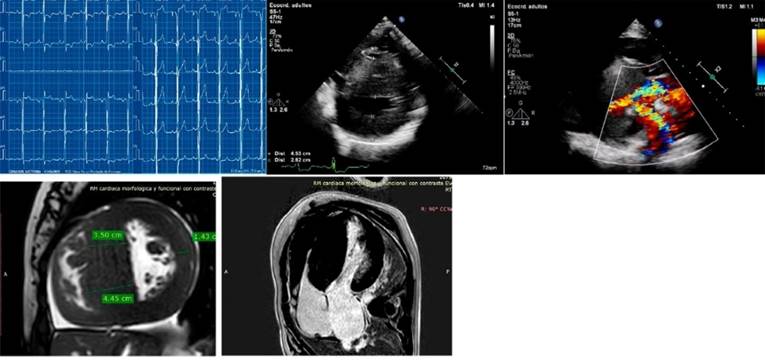

The index case is a woman with severe

hypertrophy diagnosed at the age of 37, with ICD implantation for syncopal sustained monomorphic ventricular tachycardia (VT)

at the age of 47. The CMR showed non-compacted myocardium (NCM) and G+ (MYH7:

c.1208G>A (p. Arg403Gln). Her 3 sons have G+, two of them with F+,

pathological ECG (left ventricular hypertrophy and negative T waves on the

anterolateral side). Above: ECG and CMR of one of her sons. Below: patient's

ECG and CMR.